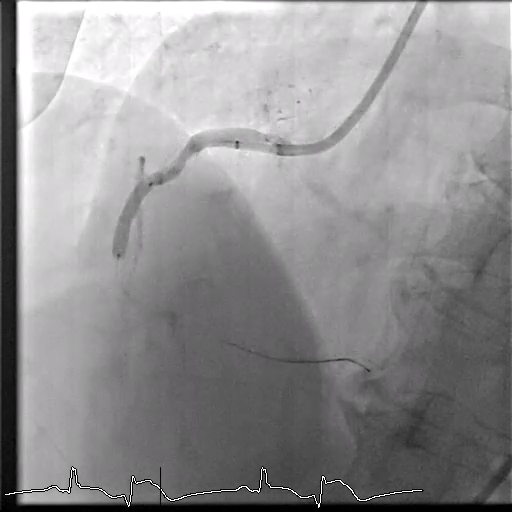

Cardiac catheterization was performed via right femoral approach with JL6/4, JR 6/4 diagnostic catheter show total occlusion mRCA, 30% stenosis at proximal-LAD, 90% stenosis at mid-LAD, 95% stenosis mid-LCx. PCI with JR 6/4. PCI to mid-RCA. GD: JR 6/4. Turntrac with Guidezilla to RCA. SC balloon 2.0x12 mm inflated mRCA up to 12 atm. Rapamycin eluting stent 3.0x18 mm deployed mRCA 12 atm with POT-PUFF sign technique. The final angiogram was acceptable result. After successful reperfusion of the right coronary artery, the premature ventricular complexes (PVCs) was subsides.

STEMI patterns can occasionally be observed during premature ventricular contractions (PVCs), which may assist in establishing the diagnosis of STEMI. It is important to take advantage of all available information, as PVCs can often provide valuable diagnostic clues.In this case, successful restoration of RCA flow resulted in resolution of conduction disturbances and PVCs. POT-PUFF sign technique during PCI. This method allows real-time confirmation of optimal stent expansion and apposition.